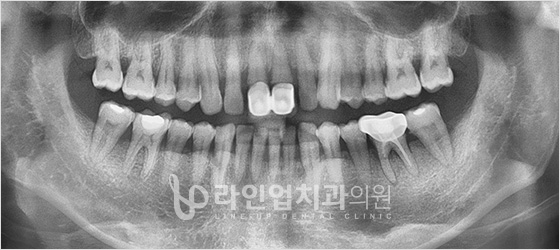

Before

After

Доод арааны имплант